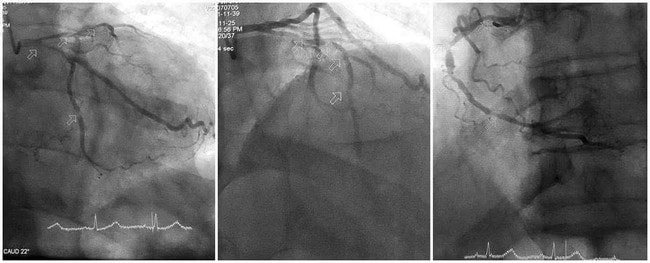

Kết quả chụp mạch vành cho thấy tổn thương nặng cả ba thân động mạch vành: động mạch liên thất trước hẹp tới 90–99%, gần như tắc hoàn toàn; động mạch mũ và động mạch vành phải hẹp 80–90%, thành mạch vôi hóa nhiều, gây khó khăn lớn cho quá trình can thiệp.

Trước tình huống đó, ê-kíp can thiệp đã nhanh chóng hội chẩn, lựa chọn chiến lược phù hợp, tập trung xử trí tổn thương nặng nhất. Bằng kinh nghiệm và sự phối hợp nhịp nhàng, các bác sĩ đã vượt qua đoạn mạch vôi hóa cứng, nong bóng và đặt thành công stent vào động mạch liên thất trước, giúp tái thông dòng máu nuôi tim.